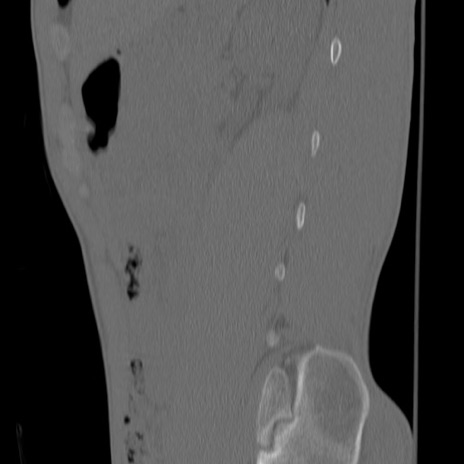

症例3 腰椎CT(矢状断像)

【症例】30歳代男性

【主訴】腰痛

【現病歴】本日旅行先で観光中に、友人と衝突し転倒し受傷。

【身体所見】麻痺なし、右下腿内側前面外側、左下腿内側に知覚鈍麻・しびれ

異常所見と診断は?

腰椎CT